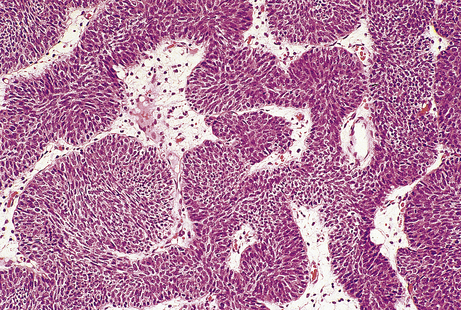

Neoplasms differ histologically from their corresponding normal tissue by various features; these are useful in diagnosis and include:

loss of differentiation

loss of cellular cohesion

nuclear enlargement

increased mitotic activity.

These features are often seen to their greatest degree in malignant neoplasms (Fig. 11.9).

image

Fig. 11.9 Histological features of neoplasia. A malignant neoplasm showing no immediately recognisable differentiated features, loss of cellular cohesion, and increased nuclear size and mitotic activity. Abnormal mitoses are present (arrowed).